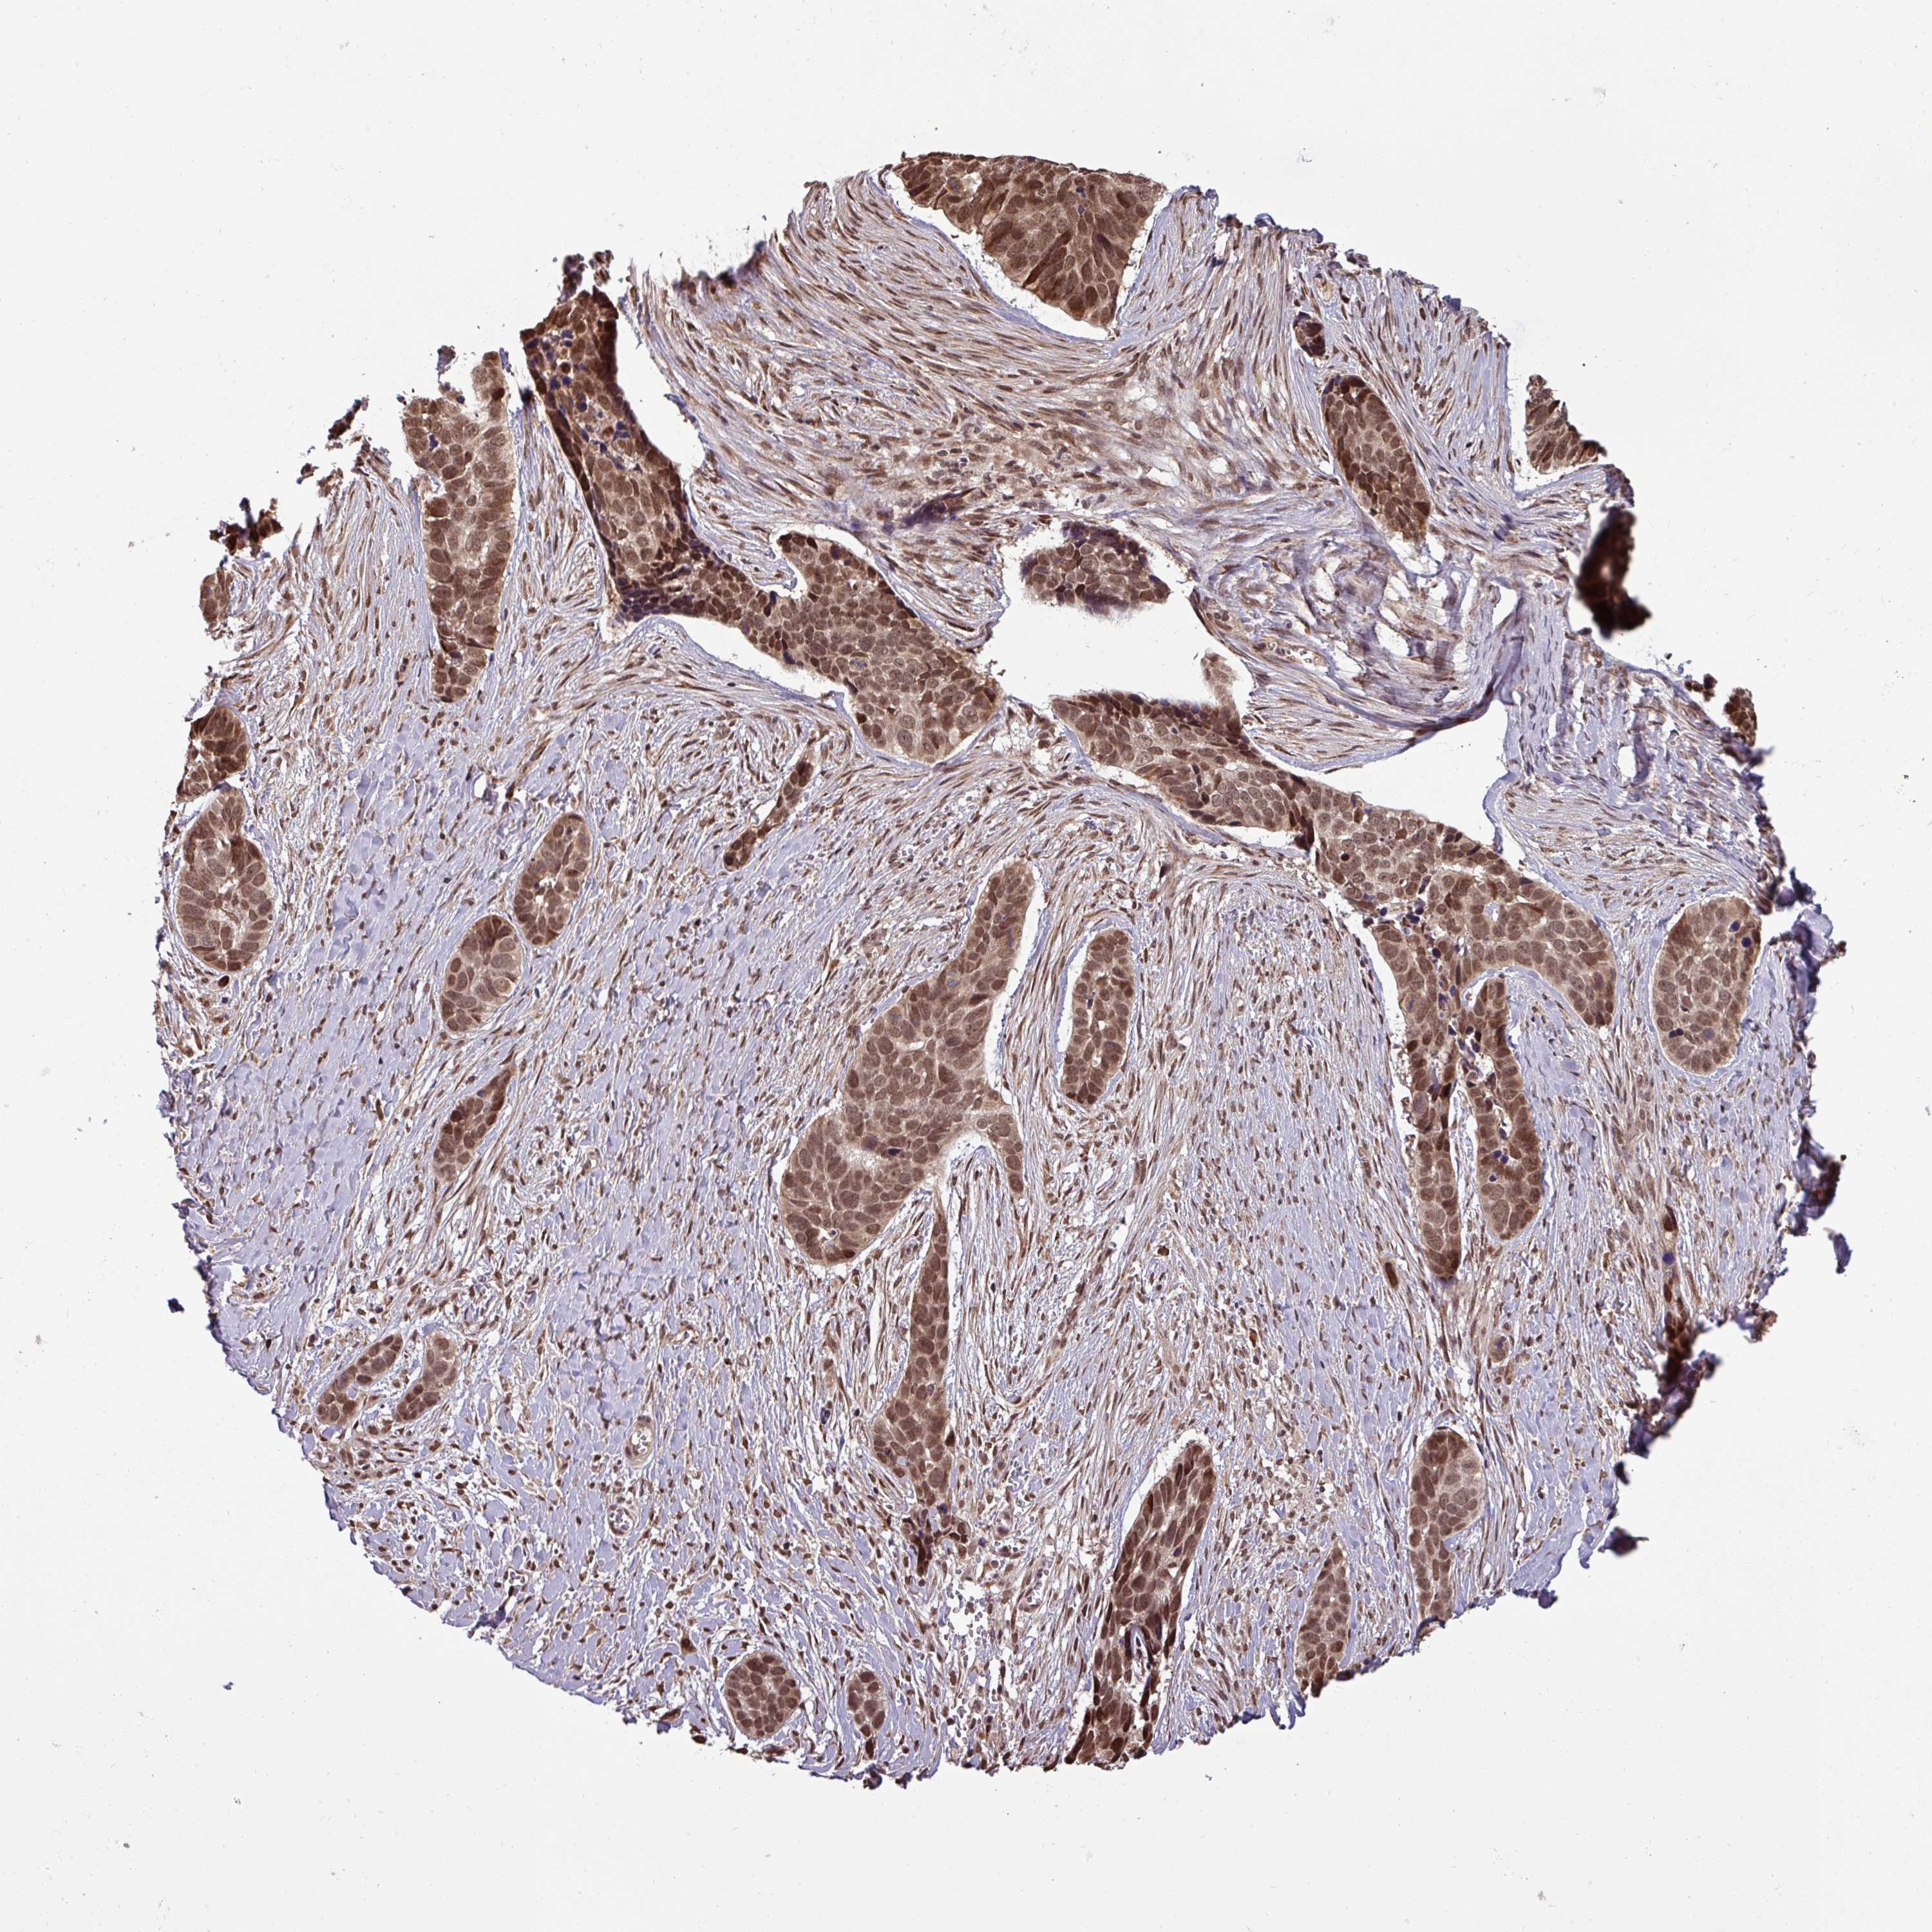

SKIN CANCER - Protein expressioni

A mouse-over function shows sample information and annotation data. Click on an image to view it in a full screen mode. Samples can be filtered based on level of antibody staining by selecting one or several of the following categories: high, medium, low and not detected. The assay and annotation is described here.

Antibody staining in the annotated cell types in the current human tissue is reported as not detected, low, medium, or high, based on conventional immunohistochemistry profiling in selected tissues. This score is based on the combination of the staining intensity and fraction of stained cells.

Each image is clickable and will lead to virtual microscopy that enables deeper exploration of all samples and also displays staining intensity scores, fraction scores and subcellular localization as well as patient and tissue information for each sample.

Antibody HPA049430

Intensity

Strong

Moderate

Weak

Negative

Quantity

>75%

75%-25%

<25%

None

Location

Nuclear

Cytoplasmic/membranous

Cytoplasmic/membranous,nuclear

Basal cell carcinoma

Squamous cell carcinoma, NOS